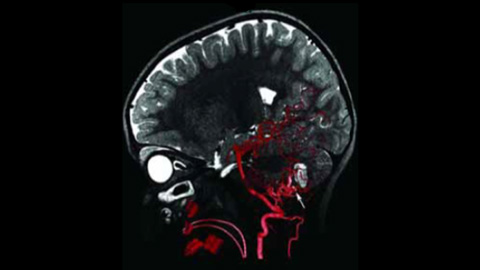

XperCT und VasoCT

Die Möglichkeit zur Darstellung der vaskulären Anatomie und endovaskulärer Materialien im Submillimeter-Bereich verbessert die Erfolgschancen und erhöht die Behandlungssicherheit. XperCT bietet CT-artige Bilder, die direkt in der Neuro Suite erfasst werden und die Identifizierung diskreter Weichgewebeläsionen erleichtern. Eine Kontrolle des Behandlungserfolgs ist somit noch im Untersuchungsraum möglich. VasoCT bietet 3D-Bildgebung mit hoher Auflösung, die wichtige zerebrovaskuläre Strukturen darstellt und so die räumliche Beurteilung von Gefäßen im Weichgewebe auf höchstem Niveau unterstützt.

3D-RA liefert in wenigen Sekunden eine volumetrische Darstellung und unterstützt so die Beurteilung von Position, Größe, Hals und Schweregrad des Aneurysmas für die Behandlungsplanung. Darüber hinaus bietet 3D-RA Volumendaten mit hoher räumlicher Auflösung und gleicht Patientenbewegungen automatisch aus.

VasoCT IA ist ein Erfassungsverfahren, das ein hochauflösendes XperCT mit Kontrastmittelinjektion kombiniert, um die Visualisierung von endovaskulären Implantaten, Flow Divertern und anderen Implantaten sowie der Gefäßmorphologie bis auf Perforatorebene zu verbessern. Es wird zunehmend für die Nachuntersuchung von mit Flow Diverter Implantaten behandelten Aneurysmen verwendet, um die Positionierung des Implantats zu überprüfen.